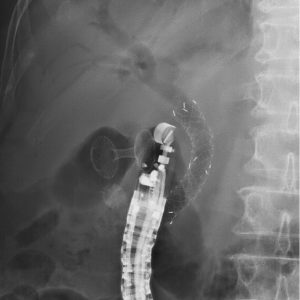

急性胆嚢炎に対するEUS下胆嚢ドレナージ(LAMS留置)